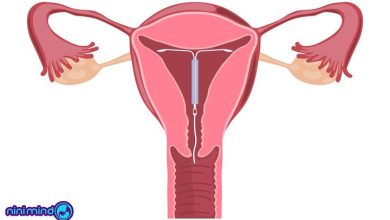

آی یو دی (IUD) چیست

آی یو دی (IUD) یکی از وسیلههایی است برای جلوگیری از بارداری از آن استفاده میشود، از آنجایی که در روشهای…